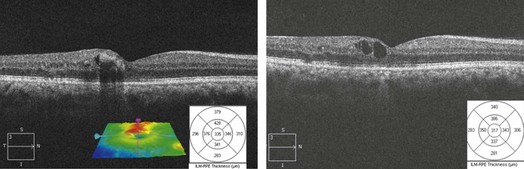

OCT shows retinal thickening and edema limited to the retinal area drained by the obstructed vein (Figs 14.1.2 and 14.1.3). Macular thickness scans will show retinal thickening, usually confined to half the macula. Line scans through the macula show diffuse retinal edema and cystic (hyporeflective) spaces in the outer retina. Subretinal fluid may also be observed in severe cases. Hard exudates can be seen as small hyper-reflective intraretinal spots. Macular thickness scans are particularly valuable in monitoring edema over time and assessing the effects of treatment.

Figure 14.1.2 OCT scans through the macula of the patient (A) with diffuse retinal thickening and cystic changes (arrows). Note the cotton wool spots (CWS) (arrows) in the nerve fiber layer that cause shadowing of the layers beneath them. Some hard exudates (HE) are noted (arrow) as hyper-reflective clusters deeper within the retina and spanning several layers. SRF is also seen (arrow). (B) Note that only part of the retina is thickened unlike in CRVO.

Figure 14.1.3 Successive OCT scans in the same patient after treatment with laser and anti-vascular endothelial growth factor therapy, with thinning of the retina seen on the line and macular thickness scans as well as a smaller geographic spread of the thickening seen on the retinal pigment membrane–internal limiting membrane overlay.